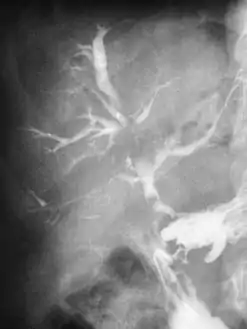

في الأشخاص الذين يعانون من الفشل الكلوي، والذين يحتاجون إلى غسيل الكلى، غالباً ما يتم إنشاء ناسور كيمينو بشكل متعمد في الذراع عن طريق جراحة قصيرة ليوم من أجل السماح بسحب الدم بشكل أسهل لغسيل الكلى. كعلاج جذري لارتفاع ضغط الدم البابي، ينتج الخلق الجراحي للناسور البابي الأجوفي تشابك بين الوريد البابي الكبدي وبين الوريد الأجوف السفلي عبر الفتحة الثربية (لوينسلو). هذا يعفي الجهاز الوريدي البابي من الضغط العالي الذي يمكن أن يسبب دوالي المريء، ورأس الميدوزا، والبواسير.